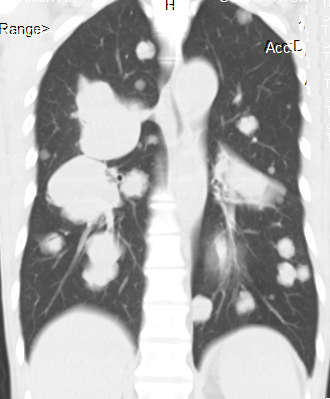

[影像描述]

双肺多发转移灶,大小不等,呈棉花团样

CT表现为粟粒、单发、多发大小不等结节,呈圆形或椭圆形,密度均匀、轮廓清楚,肺野为著。

1、肺内单发或多发球型结节影,大小不一,边缘光滑,密度均匀,多分布于肺外围

4、肺纹理呈网状改变或沿淋巴管呈细小结节状改变,HRCT表现为小叶间隔增厚,沿肺纹理有细小结节影,同一患者出现多种形态转移征象.